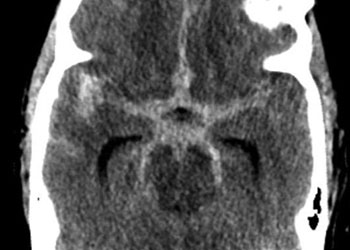

Fig 1. A) Pre-operative, post-contrast, coronal MRI. Arrow points to tumor involvement in the superior sagittal sinus. Cystic Meningiomas: Sometimes meningiomas can have partly cystic (fluid) […]